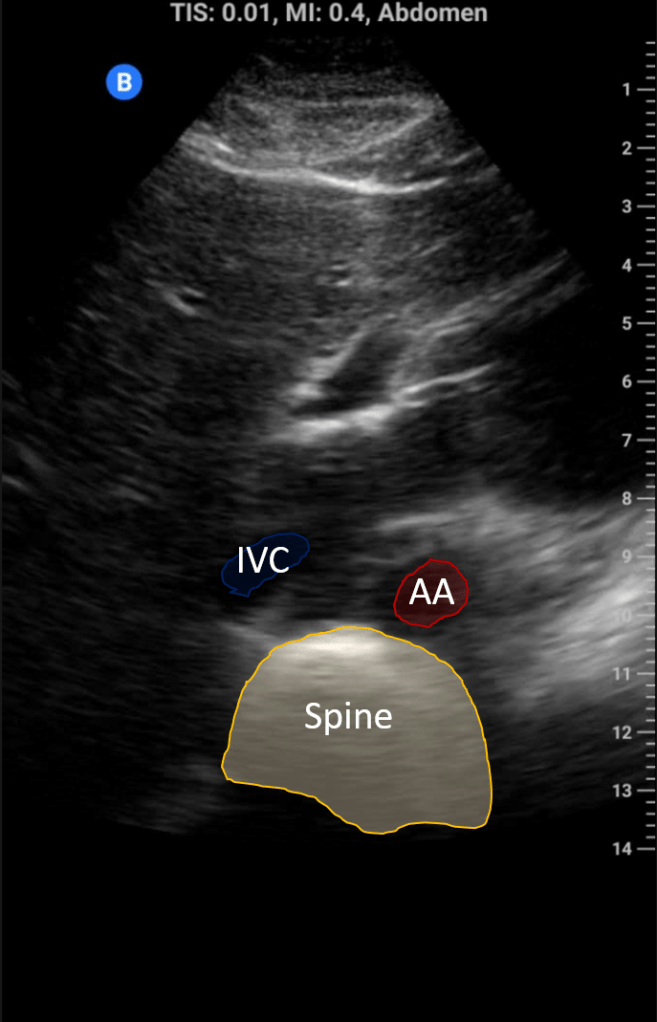

Begin in transverse; you should see the left lobe of the liver below this 2 tubular structures (IVC and aorta) and the spine below. Center the IVC and then rotate to the longitudinal view.

A common challenge in imaging the IVC is confusion with the aorta. Here are some helpful distinguishing features to avoid such an error:

IVC

- Right side

- Thin walled

- Diameter changes with respiration

- Hepatic vein drains into it

- Connects to the right atria

- Surrounded by liver

Aorta

- Left side

- Thick walled

- No change in diameter with respiration

- No hepatic vein present

- Passes “under” the heart

- No liver parenchyma below